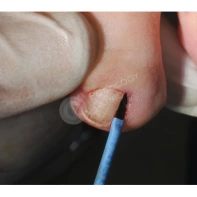

- Хирургическое иссечение. Под местной анестезией при помощи скальпеля удаляется вросший край ногтевой пластины вместе с зоной роста, затем на рану накладываются швы. В некоторых ситуациях вместе с резекцией ногтя проводится пластика околоногтевого валика, позволяющая повысить эффективность оперативного вмешательства и добиться стойкой ремиссии заболевания.

- Лазерная резекция. Лазером удаляется вросший кусочек ногтя и поврежденные слои ногтевого валика. Затем прижигается разросшийся участок ростковой зоны. При этом лазерные пучки одновременно стерилизуют ногтевое ложе, исключая риск развития инфекционных процессов и ускоряя процесс заживления. Операция занимает 15–20 минут, имеет минимальную травматичность. Период восстановления после такого вмешательства относительно короткий.

- Непосредственное удаление патологически измененных тканей.

- Обработка раны и наложение стерильной повязки.

Лечение вросшего ногтя СО2-лазером

Пациентам с обострением вросшего ногтя, который беспокоит длительное время, может быть показано выполнение краевой резекции СО2-лазером. Облегчение и снижение болевого синдрома наступает непосредственно после вмешательства. Подробнее об операции рассказывает хирург-онколог Георгий Исаевич Исмаилов.